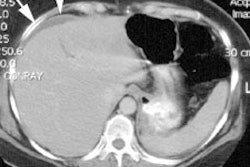

Budd-Chiari Syndrome (Hepatic Vein Thrombosis)

Patients with Budd-Chiari typically present with hepatomegaly (due to congestion) and ascites.

Scintigraphic findings early in the disorder are characterized by a diffusely mottled tracer uptake in the liver. Over time this will progress to diffusely decreased activity. The caudate lobe will usually enlarge and show relatively increased activity as a result of its separate venous drainage directly into the IVC. If inferior vena caval obstruction is present, the scan will show diffuse hepatocellular dysfunction.